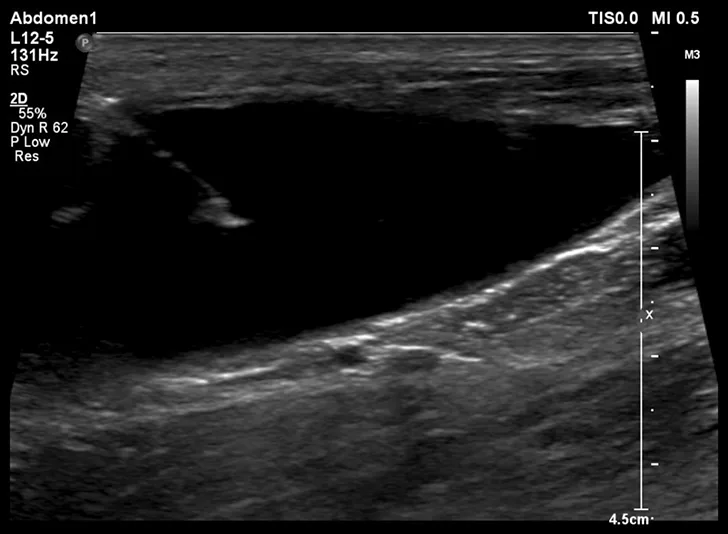

FIGURE 1

Ultrasonographic image showing the cranial aspect of the urinary bladder (A), identified just before ultrasound-guided cystocentesis. It is important to adjust the depth of the image so that the urinary bladder is focused and to consider the depth of the urinary bladder using a machine scale that should be present on the ultrasound screen; in smaller patients the needle may only be partially inserted and not reach the hub (B; arrow).